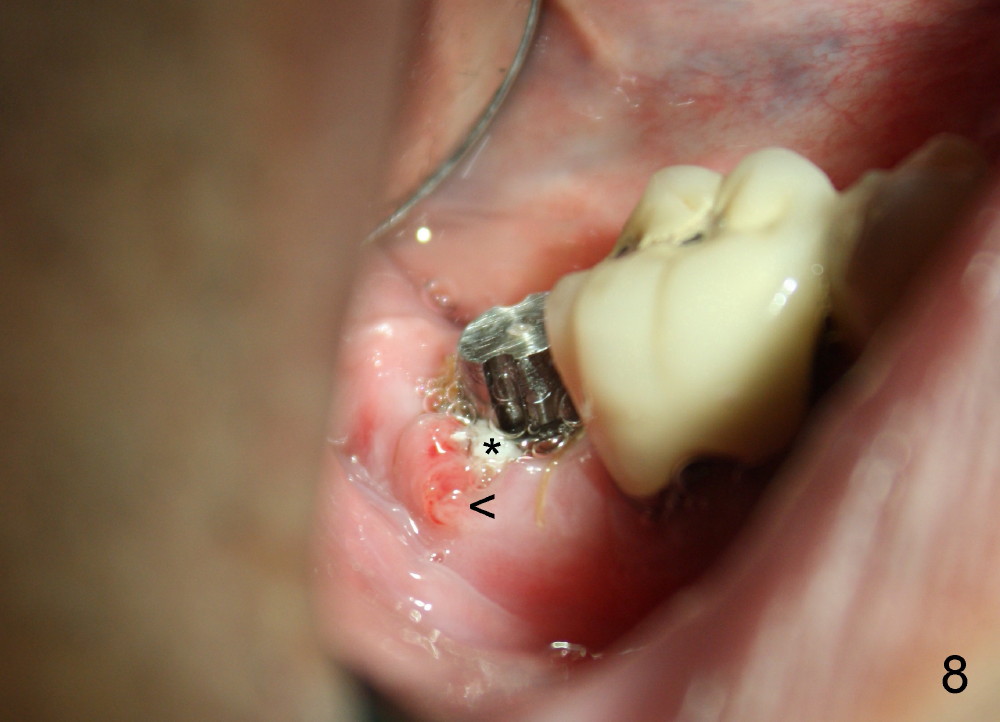

A 51-year-old man has experienced pain and swelling in the lower right 2nd molar for 7 months (Fig.1, P: post in the mesial root; <: gutta percha inserted into a buccal fistula). Fig.2 is taken immediately before extraction (<: purulent discharge from the mesiobuccal fistula) and immediate implant (Fig.3 implant design: 7x14 mm). A vertical root fracture is noted in the mesial root (Fig.4: lingual view). The septum is in fact absent, as compared to Fig.1. The mesiobuccal plate is low; the osteotomy starts lingual to the center of the socket. Fig.5 shows a 4.5x17 mm tap in place: approximately 3.5 mm in the new bone (~2.5 mm from the inferior alveolar canal). When a 7x17 mm tap (14 mm from the gingival margin) is placed in the socket, it looks relatively small. Fig.6 shows a 8x14 mm implant in place with a small gap distally. Mineralized cancellous allograft and Osteogen mixture is placed mainly buccally, followed by a thin strip of collagen dressing and sutures (Fig.7); an abutment (A) is placed to keep perio dressing in place. The perio dressing does not stay long. The buccal portion dislodges by itself 5 days postop. The lingual portion is removed in clinic. New dressing is going to be re-applied, because the buccal wound has not completely healed (Fig.8 <, albeit asymptomatic) with partial exposure of the bone graft (*). Why is the dressing lost so early? The abutment is not long enough; there is plenty of occlusal clearance (Fig.9 arrows). A longer abutment is used to increase mechanical retention for perio dressing (Fig.10). By the time the second perio dressing dislodges, the wound has healed (Fig.11, 13 days postop).